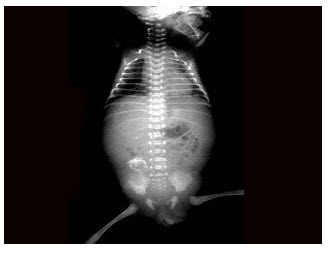

128、单项选择题

男,出生后2天。哭闹不止,腹胀。如图所示,最可能的诊断为()

A.肠套叠

B.肠闭锁

C.胎粪性腹膜炎

D.肠扭转

E.肠狭窄

点击查看答案